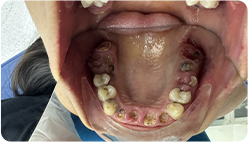

Sau khi chụp X-quang và quan sát trực tiếp,

răng của Ngân đang gặp các vấn đề nghiêm trọng

Hàm trên mất 2 răng do tai nạn giao thông, và 2 năm sau, chân của 2 răng bị lủng, gãy

8 răng bị hư cần điều trị tủy: Răng số 15, 12, 21, 22, 25, 31, 41, 45

Hàm dưới 10 chân răng bị hư nặng, mất chân răng, cần phải nhổ răng số 11, 17, 16, 25, 27, 26, 37, 38, 46, 47